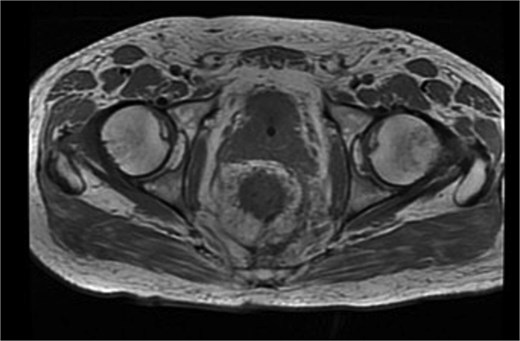

Histopathological analysis revealed a moderately differentiated adenocarcinoma. Colonoscopy showed no additional lesions and tumour markers were normal. PET-CT excluded distant disease. Pelvic MRI demonstrated involvement of the left levator ani, mesorectal fascia, and suspicious lymph nodes, suggestive of cT4bN1a disease (Fig. 4).